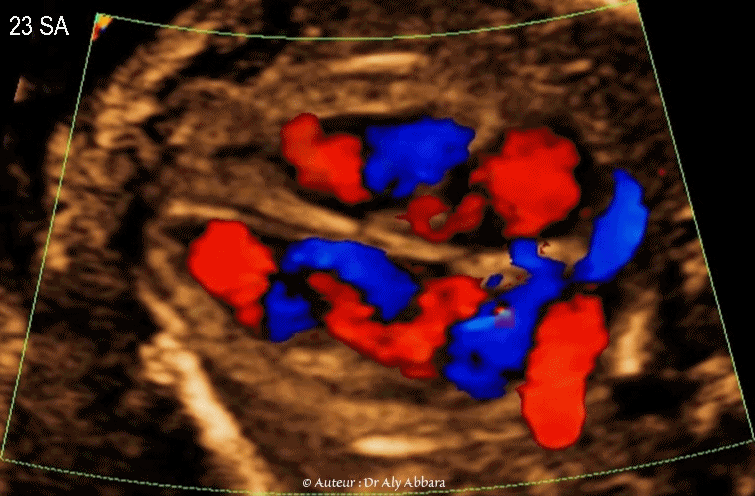

Image échographique animée montrant à l'aide du Doppler-couleur le retour veineux vers l'oreillette gauche durant la vie in-utero - والعود الوريدي نحو الأُذينة اليسرى أثناء الحياة الجنينية

Images échographiques animées montrant à l'aide du Doppler-couleur le retour veineux vers l'oreillette gauche "OG" chez le fœtus ; il est composé :

I- Du retour veineux pulmonaire via les quatre veines pulmonaires (deux veines droites et deux veines gauches).

Sur ces images on identifie une veine pulmonaire gauche "VPG" et une pulmonaire droite "VPD"

II- Du flux sanguin veineux prévenant de l'oreillette droite "OD" via le foramen ovale "FO" ; une grande partie de ce flux sanguin provient du canal veineux (sang oxygéné) qui se jette dans la portion terminale de la veine cave inférieure, juste avant sa connexion à l'oreillette droite.

Ce shunt droit-gauche disparaît rapidement après la naissance par l’augmentation de la pression dans l'oreillette gauche (comparé à l'oreillette droite) qui aboutit à la fermeture du foramen ovale par la valvule de Vieusens.

Fœtus âgé de 23 SA